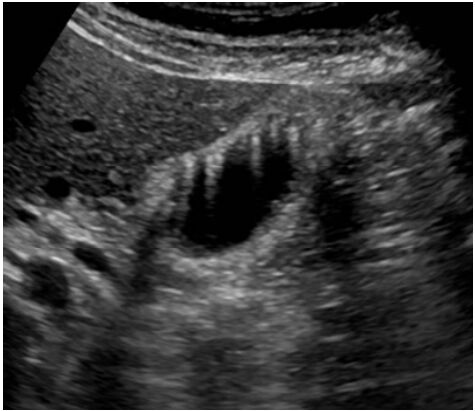

63.下圖為右上腹部超音波影像,其最可能的診斷為下列何者?

(A)膽結石 (B)膽囊壁水腫 (C)膽囊腫瘤 (D)正常腎臟